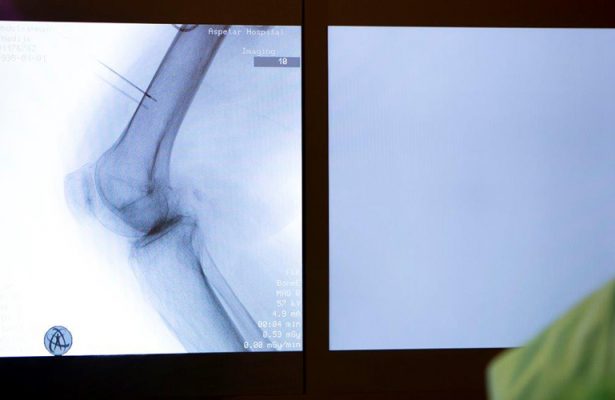

Aspetar, one of the leading sports medicine hospitals in the world, recently introduced a Cooled Radiofrequency (C-RF) treatment, an innovative option for helping resolve joint and spinal pain conditions. Cooled Radiofrequency is a minimally invasive treatment option targeting nerves that transmit pain signals. It can bring non-surgical relief to those suffering from chronic pain in some cases resulting from surgery, trauma or osteoarthritis. Dr Yasin S. Al Makadma, Consultant Pain Management at Aspetar, said: “Radiofrequency (RF) treatment procedures consist of applying a strong,